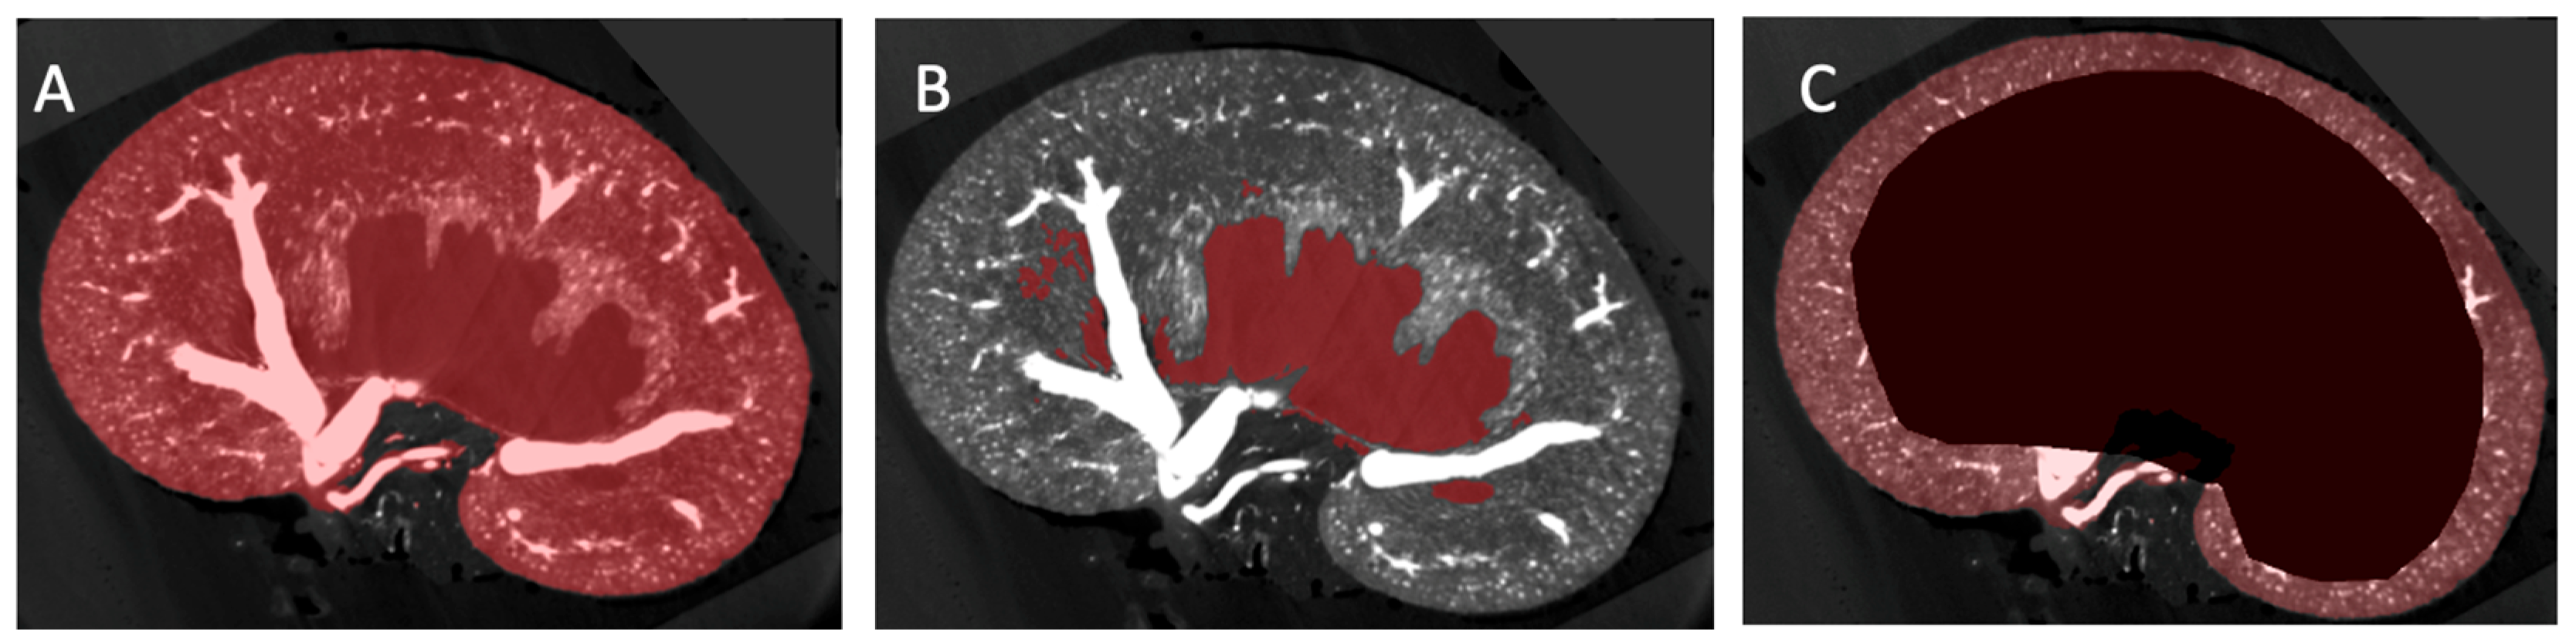

2.2. Image Segmentation and Vascular Density Measurement

3.2. Vascular Modelling of Diabetic Kidney Disease